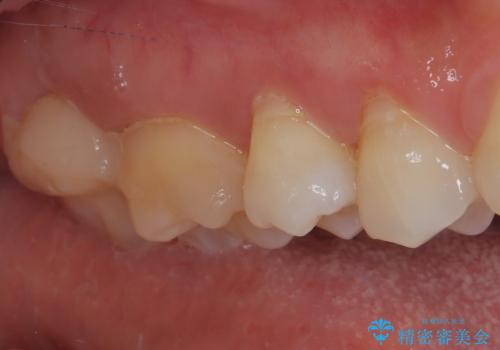

食事をすると痛む奥歯 オールセラミッククラウンでのむし歯治療

- 上顎大臼歯が食事の度に痛みを感じるとのことで来院された患者様です。

レントゲン写真などで診査を行ったところ、神経組織が壊死し、根尖部周辺の骨に炎症が認められました。

まずは根管治療を行い、症状が消退したことを確認してオールセラミッククラウンにて補綴治療を行うこととしました。